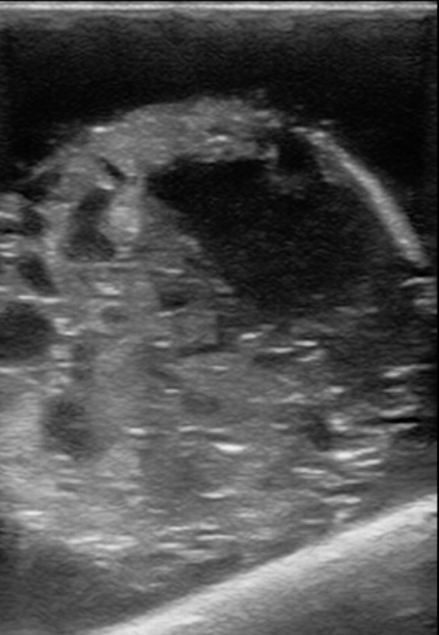

Figure 17. A model with an extra outer balloon and the inner contents ruptured with a skewer. Used as an example of testicular rupture.

Figure 18. A model with half the recommended concentration of gelatin used. Blunt trauma was then applied by bouncing the balloon gently several times and then placed in the refrigerator. The result was used as a model for testicular rupture, but did not require a skewer.